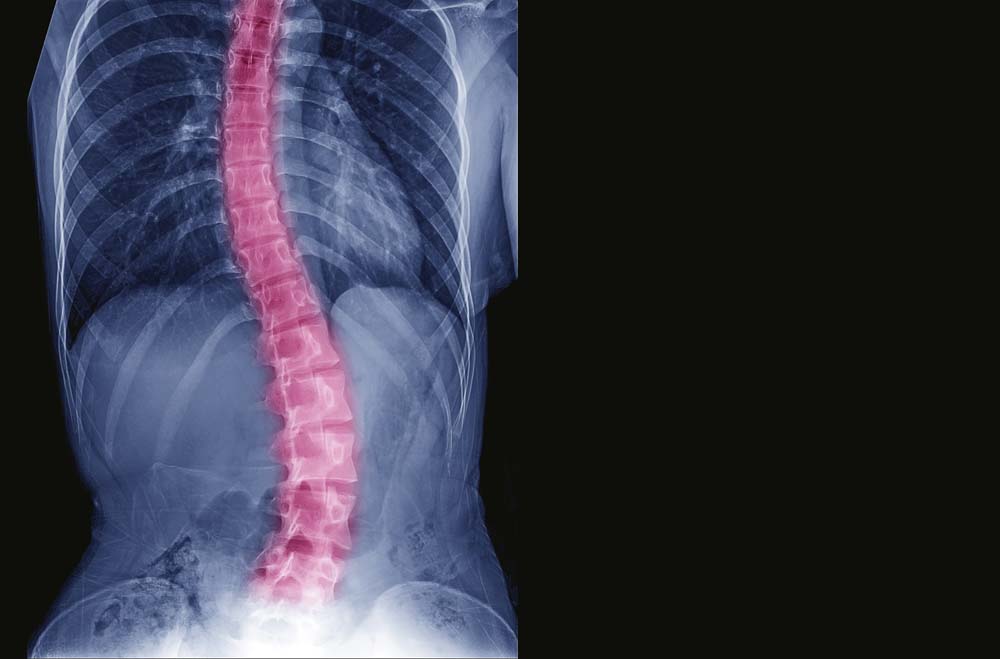

Lumbar Scoliosis X Ray Vertebral Disc Scoliosis Depending on where the herniated. This is due to the compression of nerves or spinal cord by the bulging disc. A herniated disk, which can occur in any part of the spine, most often occurs in the lower back. In this stage, the outer layer of the disc may develop a. Certain neuromuscular conditions, such as cerebral palsy or muscular.. Vertebral Disc Scoliosis.

From www.floridaortho.com